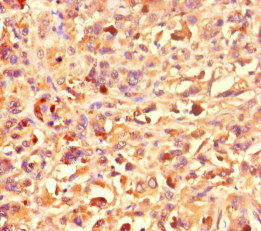

應用范圍:ELISA, IHC

Application Recommended Dilution IHC 1:20-1:200 -